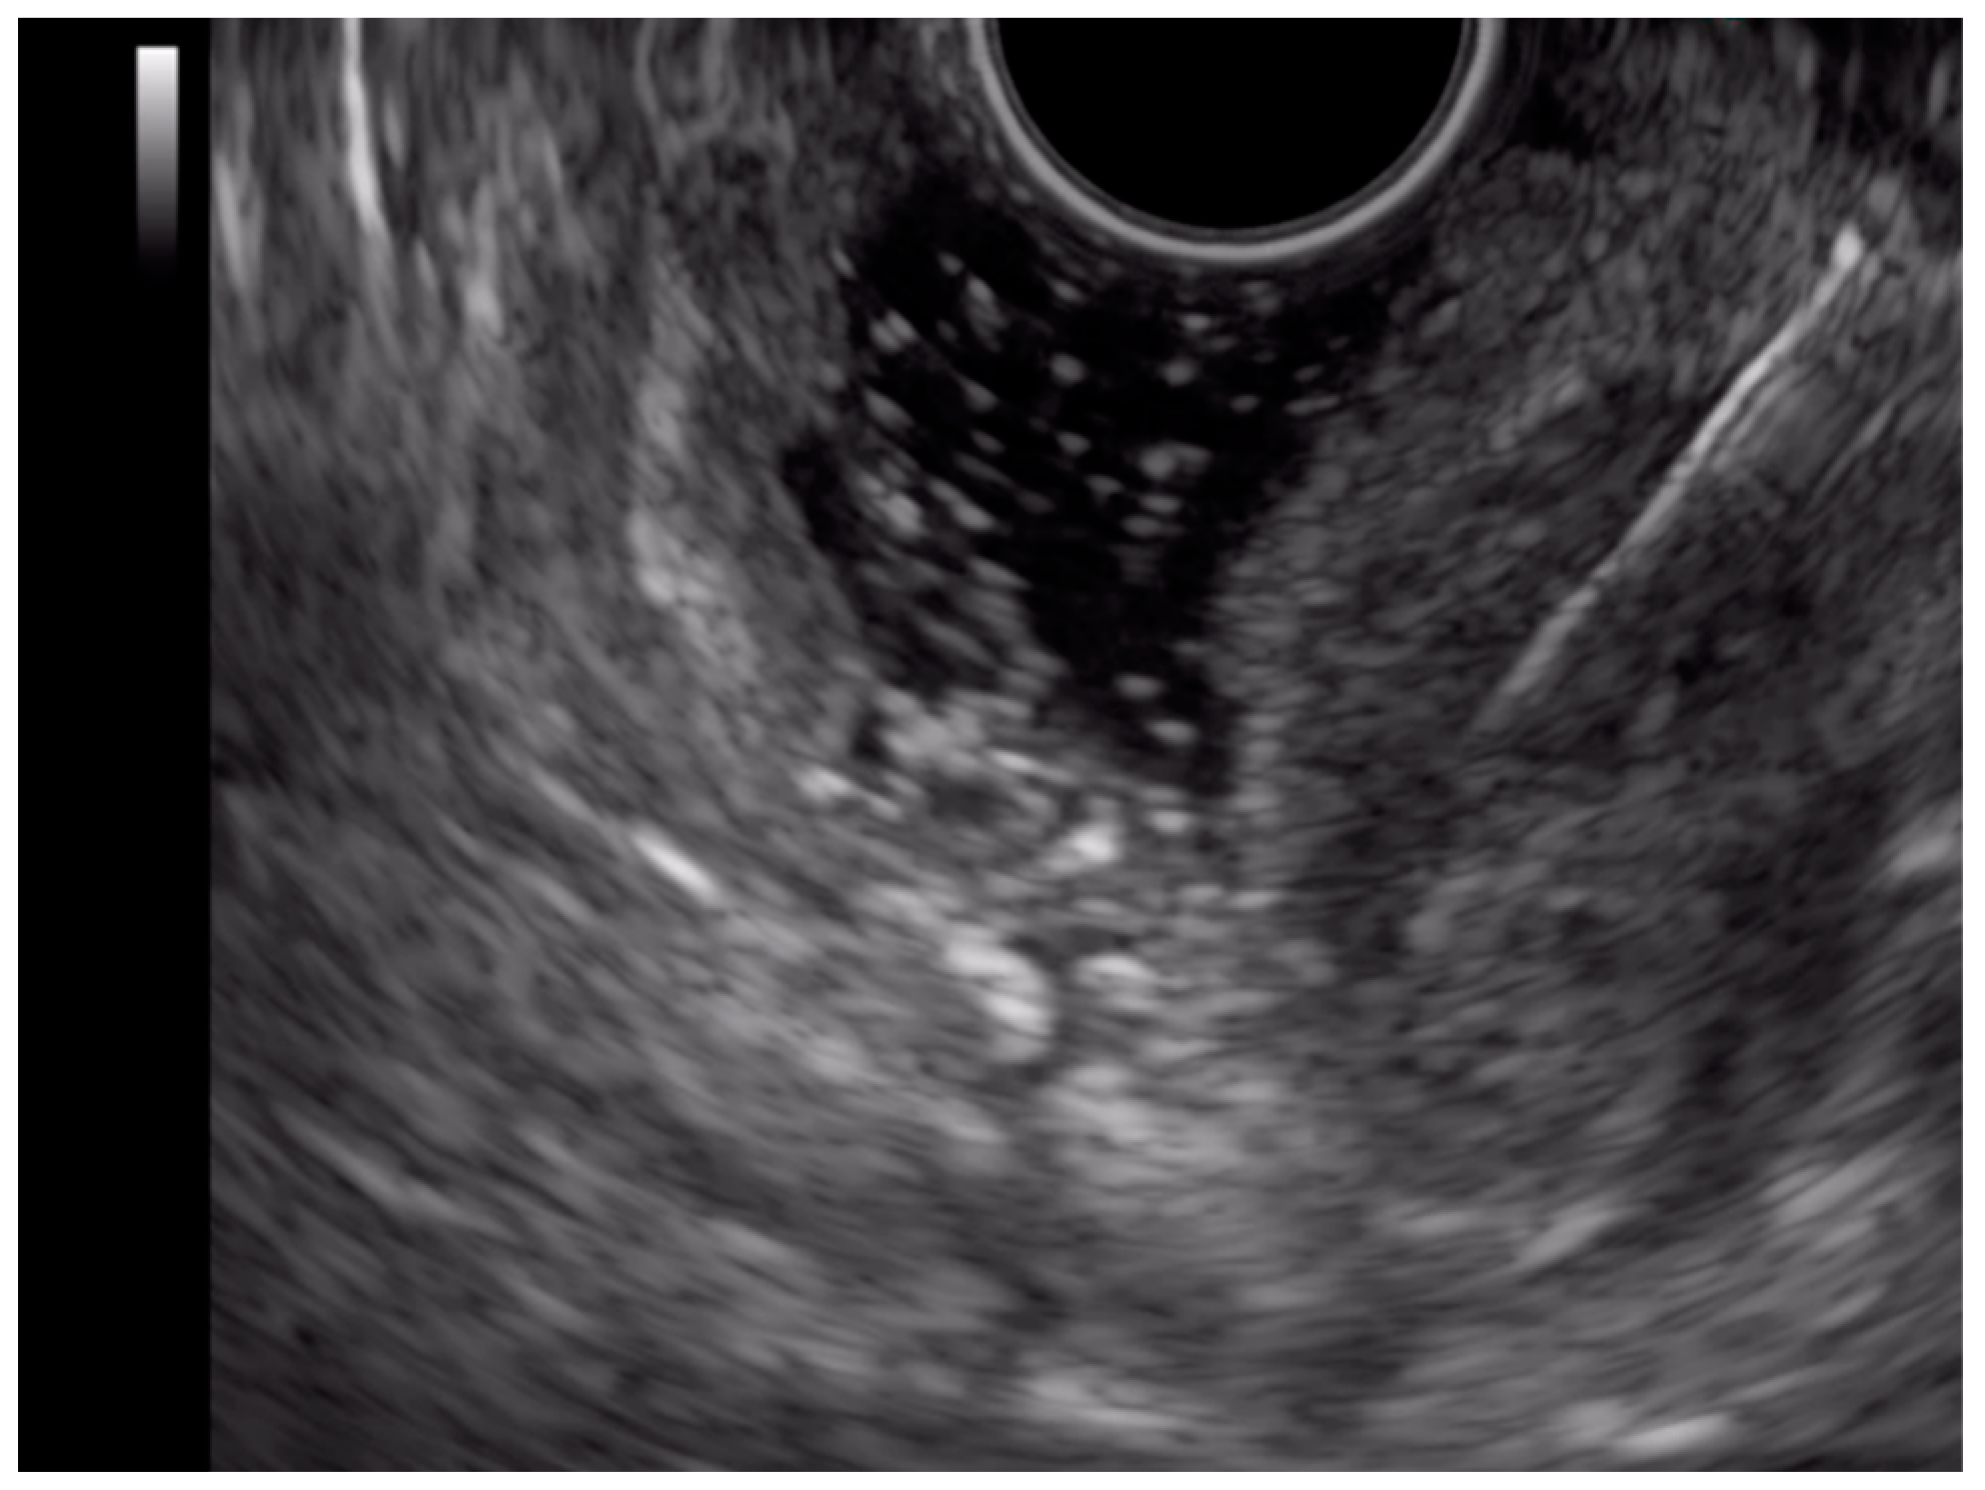

2.2. Upper Enteroscopy

2.3. Endoscopic Ultrasound (EUS)